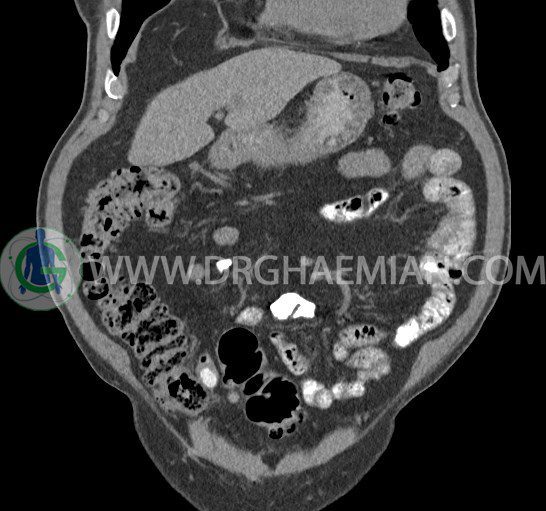

سی تی اسکن لگن یکی از روش های تصویربرداری با سی تی اسکن است. این روش با استفاده از تشعشعات تصاویر عرضی از ناحیه شکمی ایجاد میکند. در این کیس ديورتيكولوزيس، کیست های کورتیکال در هر دو کلیه، لنفادنوپاتی، کلسیفیکاسیون دیواره آئورت و شریان ایلیاک، تغییرات DJD ناحیه توراکولومبار و پروستات بزرگتر از عادی دیده می شود.

در سي تي اسکن اسپيرال شکم و لگن با و بدون کنتراست خوراکی و وريدی (مولتي ديدکتور 16 با مقاطع ظريف و بازسازي هاي ساژيتال و کرونال):

– کيست هاي کورتيکال ساده به قطر 5 mm تا 50 mm در کليه راست و به قطر 5mm تا 55 mm در کليه چپ

– توده ايزودنس به ابعاد mm 17 x 28 در پره ائورت مجاور قسمت تحتاني D3 دئودنوم مطرح کننده لنفادنوپاتي و با احتمال کمتر آنوريسم ترومبوزه (نيازمند مطابقت سونولوژيک)

– کلسيفيکاسيون ديواره آئورت و شريان ها ايلياک همراه با نشانه هاي ترومبوز مورال در بيفورکاسيون ائورت با امتداد به پروگزيمال هاي شريان هاي ايلياک

– ديورتيكولوزيس در کولون نزولي وسيگموئيد

لنفادنوپاتي به ابعاد mm 22 x 25 مجاور شريان ايلياک خارجي چپ و به ابعاد mm 17 x 28 مجاور شريان ايلياک خارجي راست

– تغييرات DJD در ناحيه توراکولومبار و

– پروستات به ابعاد mm 45 x 54، بزرگ تر از نرمال

مشهود است.